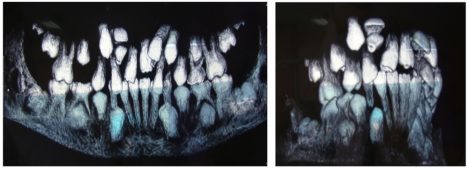

Двустранно дистализиране на молари

Дистализирането на моларите е ортодонтска процедура, която се прави за увеличаване периметъра на зъбната дъга в задните сегменти. Горните молари се придвижват дистално и се коригират клас II съотношенията при моларите. Използва се постигнатото място за подреждане на зъби в средния или фронтален сегмент.